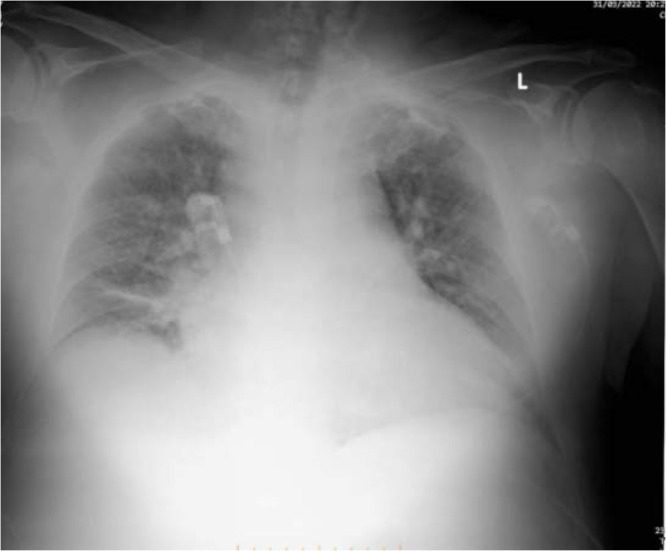

Systolic anterior motion (SAM) of the mitral valve refers to the unusual movement of the anterior and sometimes the posterior mitral valve leaflets toward the left ventricular outflow tract (LVOT) during systole. This phenomenon is most frequently associated with the asymmetric septal variant of hypertrophic cardiomyopathy (HCM), but it can also occur in conditions like acute myocardial infarction, diabetes mellitus, hypertensive heart disease, after mitral valve repair, and even in asymptomatic individuals during dobutamine stress tests. We present a case of transient SAM induced by a junctional rhythm along with high doses of dobutamine and nitroglycerin in an intensive care unit (ICU) setting. Transesophageal echocardiography (TEE) played a crucial role in detecting SAM and showed that transitioning from a junctional rhythm to a ventricular paced rhythm led to an improvement in the SAM condition.

Abstract Image